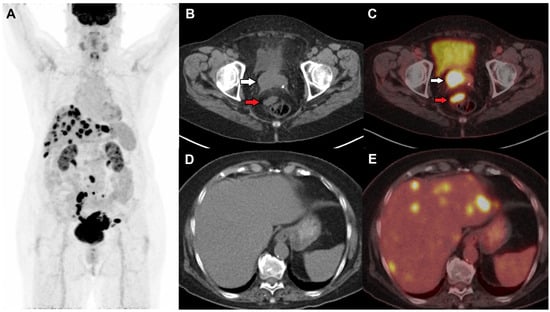

2. FDG PET/CT in Cervical Cancer

2.1. FDG PET in Staging

- Gandy, N.; Arshad, M.A.; Park, W.-H.E.; Rockall, A.G.; Barwick, T.D. FDG-PET Imaging in Cervical Cancer. Semin. Nucl. Med. 2019, 49, 461–470. [Google Scholar] [CrossRef]

- Fleming, S.; Cooper, R.A.; Swift, S.E.; Thygesen, H.H.; Chowdhury, F.U.; Scarsbrook, A.F.; Patel, C.N. Clinical Impact of FDG PET-CT on the Management of Patients with Locally Advanced Cervical Carcinoma. Clin. Radiol. 2014, 69, 1235–1243. [Google Scholar] [CrossRef] [PubMed]

- Lin, A.; Ma, S.; Dehdashti, F.; Markovina, S.; Schwarz, J.; Siegel, B.; Powell, M.; Grigsby, P. Detection of Distant Metastatic Disease by Positron Emission Tomography with 18F-Fluorodeoxyglucose (FDG-PET) at Initial Staging of Cervical Carcinoma. Int. J. Gynecol. Cancer 2019, 29, 487–491. [Google Scholar] [CrossRef] [PubMed]

- Gee, M.S.; Atri, M.; Bandos, A.I.; Mannel, R.S.; Gold, M.A.; Lee, S.I. Identification of Distant Metastatic Disease in Uterine Cervical and Endometrial Cancers with FDG PET/CT: Analysis from the ACRIN 6671/GOG 0233 Multicenter Trial. Radiology 2018, 287, 176–184. [Google Scholar] [CrossRef] [PubMed]